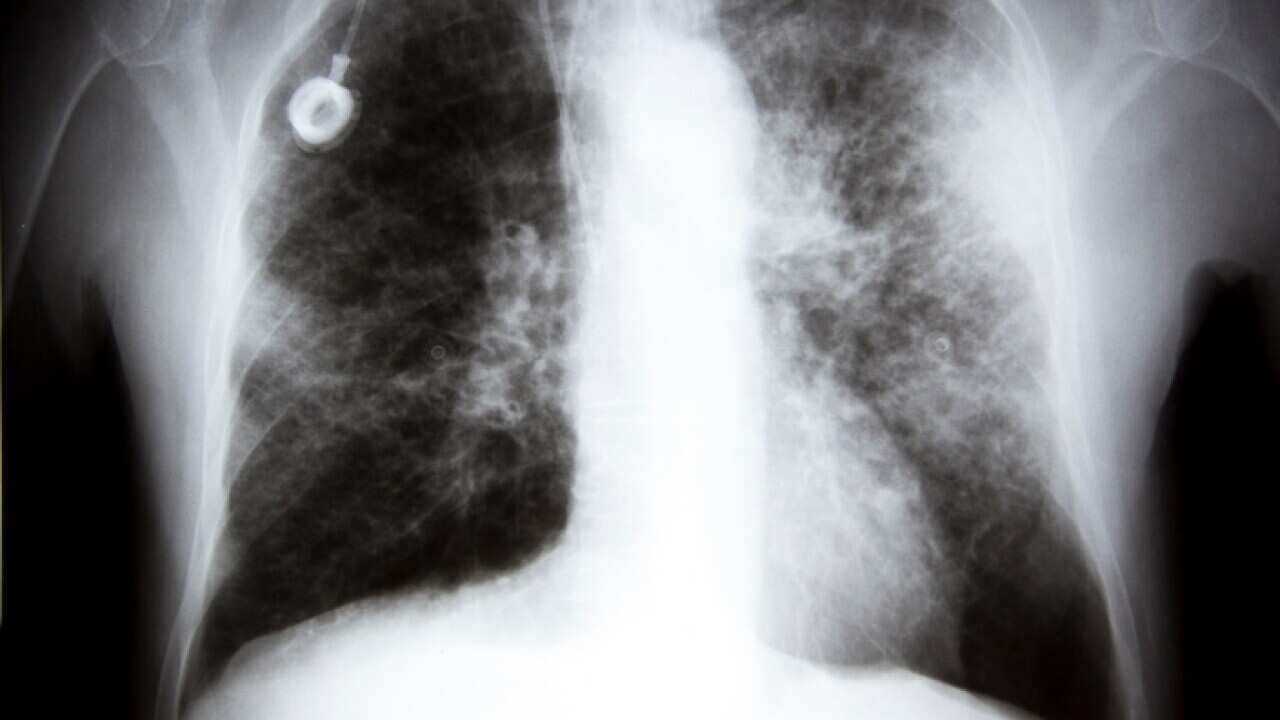

An X-ray showing lung cancer Source: Getty

Screening for lung cancer has long been seen as too expensive and sometimes too unreliable. But with the disease now recognised as the deadliest type of cancer in Australia, experts are urging a lifesaving rethink on how to detect it early.